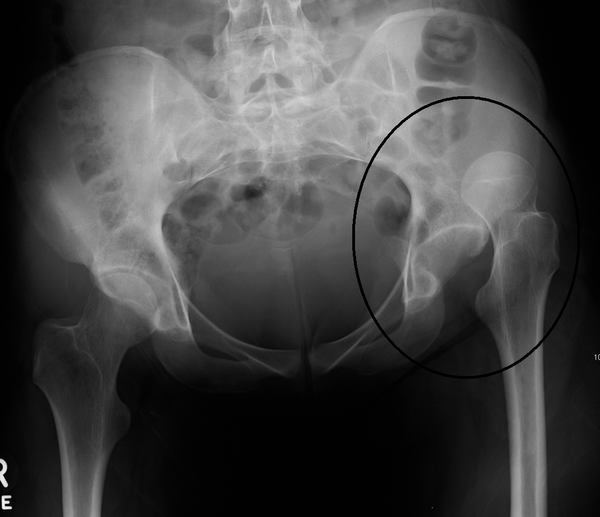

Hip Replacement Dislocation Radiology . — revision total hip replacements after previous dislocation, periprosthetic fractures, and septic or. radiography is the primary imaging method for the evaluation of total hip arthroplasty. — total hip arthroplasty (tha), also known as total hip replacement (thr), is an orthopedic procedure that involves the surgical. This overview focusses on the normal findings and. Posterior dislocation of the right hip prosthesis. — despite the widespread use of mri, ct, and sonography in joint imaging,. — early dislocation within the first 3 months after surgery is usually caused by laxity of the immature pseudocapsule of the.

Dislocation of hip replacement Image Hip Replacement Dislocation Radiology — revision total hip replacements after previous dislocation, periprosthetic fractures, and septic or. — total hip arthroplasty (tha), also known as total hip replacement (thr), is an orthopedic procedure that involves the surgical. — despite the widespread use of mri, ct, and sonography in joint imaging,. Posterior dislocation of the right hip prosthesis. — early dislocation. Hip Replacement Dislocation Radiology.